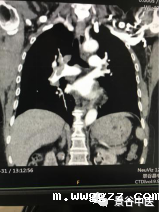

影像资料

经肺部CT报告诊断左右肺动脉主干远端、左肺上叶及双肺下叶肺动脉叶、段级分支多发肺栓塞。科主任到场看过患者,结合影像诊断,明确该患者为急性肺栓塞,积极给予了低分子肝素抗凝等综合治疗,因条件有限,立即与普洱市人民医院呼吸科取得联系,并汇报的病史和治疗方案,将患者第一时间转到普洱市人民医院呼吸科ICU,经上级医院反馈,急性肺栓塞的诊断是正确的,经治疗患者目前病情平稳;通过多学科联动,开通绿色通道,快速诊断这一症状不典型的急性肺栓塞病例,并做出相应治疗,为患者抢回最佳治疗时间。